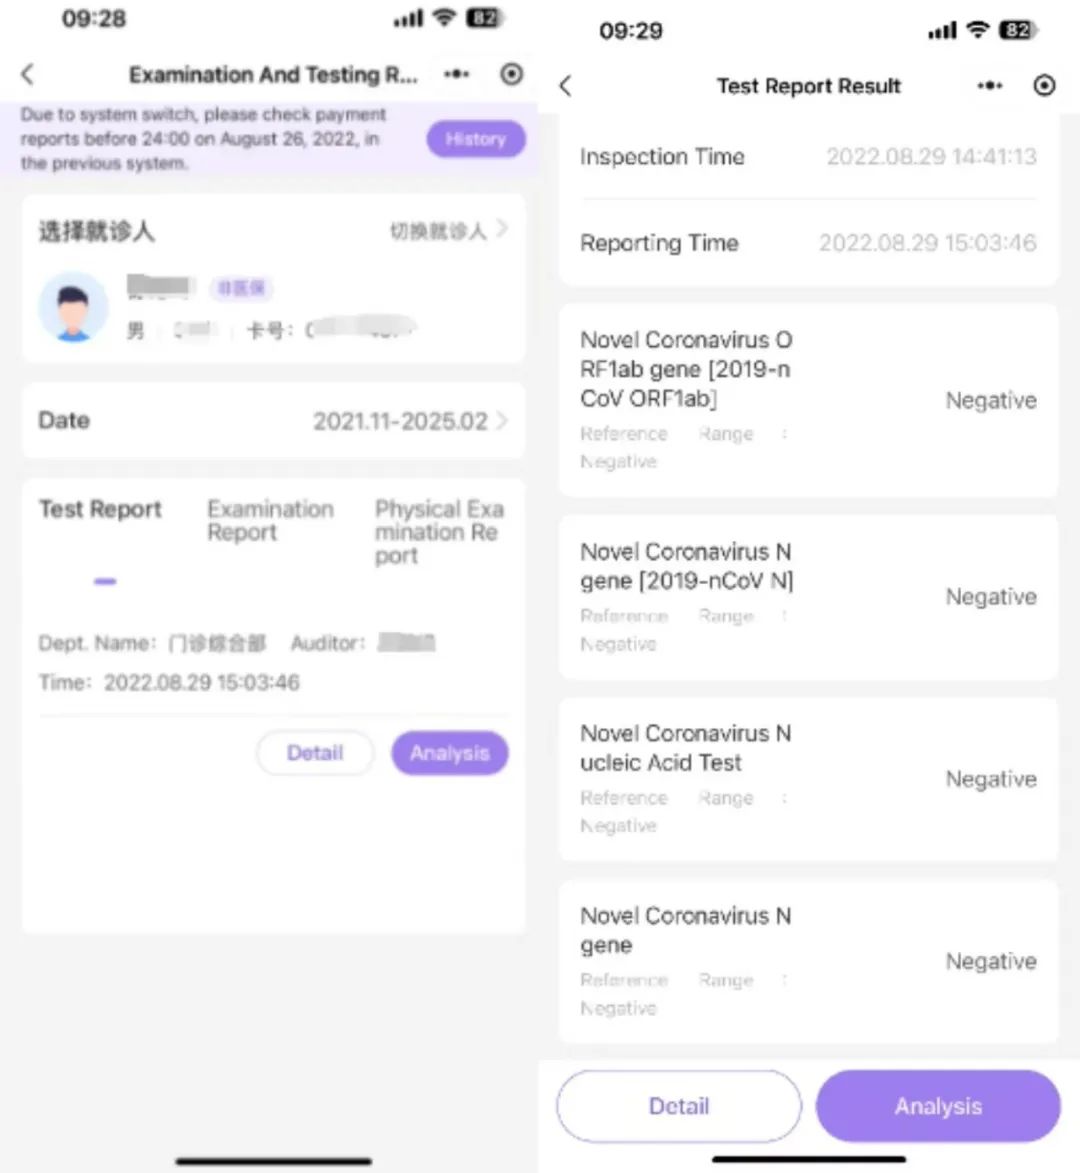

通过自主研发与生态合作双轮驱动,将AI技术融入诊疗全流程,致力于为患者和医护人员提供更加便捷、高效的解决方案,推动医疗健康事业的创新变革与高质量发展。